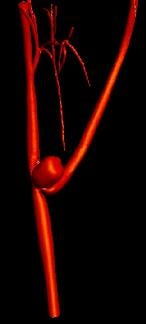

Mission: NECSTR is a neuroradiology facility that offers the latest technology in image guided intervention to support University investigators in developing minimally invasive treatments.

NECStR has been fully operational since May 3 2007 with a special focus is on image guided interventions for minimally invasive treatment of vascular disease. The center’s expertise and resources enable animal modeling of vascular pathologies, 3D x-ray imaging, post acquisition image processing, rapid prototyping from medical imaging and image guided minimally invasive surgery. Although the center’s focus lies in cardiovascular imaging and intervention, previous work has included selective vascular drug delivery for cancer treatment and orthopedic device implantation.